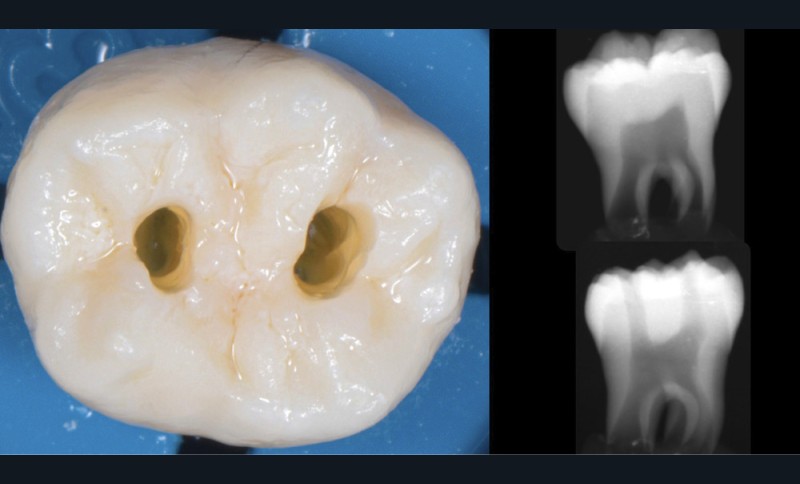

Une cavité d’accès trop petite [2] optimiserait le pronostic biomécanique (préservation dentaire maximale) mais pourrait compromettre le pronostic endodontique : mauvaise lecture de l’anatomie, instrumentation partielle, non ergonomique et avec risque de fracture, défaut de nettoyage des parois canalaires [3], irrigation inadéquate, difficulté d’obturation canalaire, voire d’obturation coronaire. Ce sera le cas des cavités d’accès « Ninja » [4] ou ultraconservatrice (fig. 1), des cavités d’accès « Truss » [5] (fig. 2), des cavités d’accès dites « opportunistes » [6] (fig. 3).